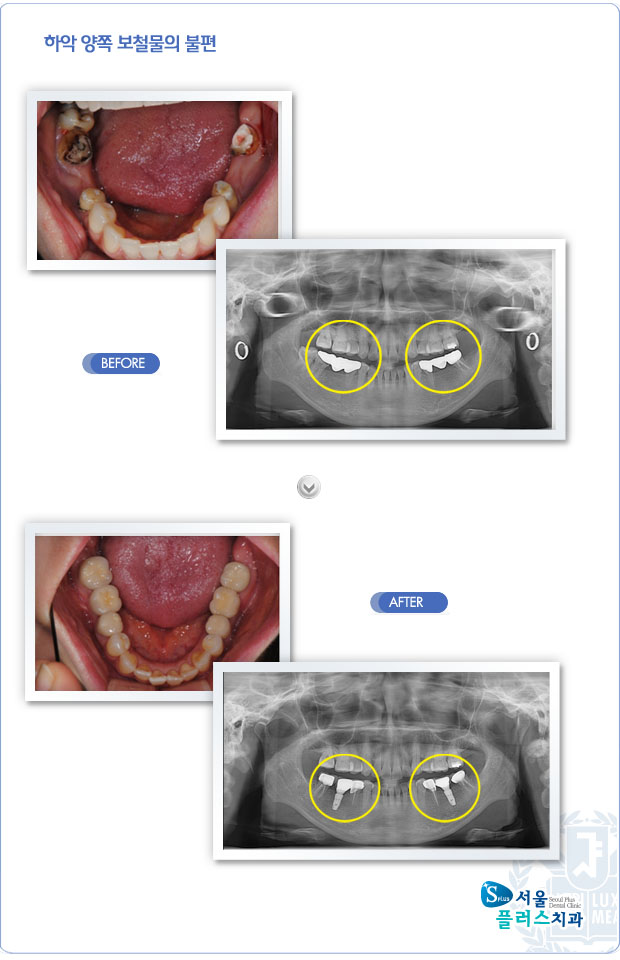

[임플란트] 하악 양쪽 보철물의 불편